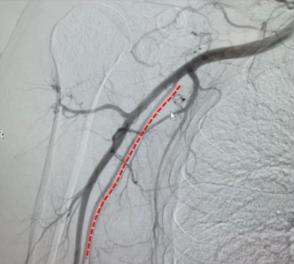

桡动脉(RA)解剖结构的经超声预可视化,以便提前了解未来引导中任何可能出现的困难,如回路、斑块或解剖变异。

应将桡动脉的影像移至至手腕上方几厘米处。 该图像展示了相关解剖结构